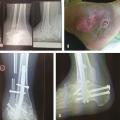

Les infections osseuses peuvent atteindre, dans le cas d’une ostéo-arthropathie de Charcot de la cheville, les malléoles ou le bord externe du pied, voire plus rarement entraîner une ostéo-arthrite tibio-talienne ou sous-talienne. Le traitement consiste là encore à débrider la plaie infectée et à exciser l’os infecté mais aussi à réaligner la cheville pour permettre la disparition de l’appui inadapté et permettre des appuis de meilleure qualité grâce à une pan-arthrodèse de l’arrière-pied dont l’ostéosynthèse par clou transplantaire est la technique la plus utilisée (fig. 4 ).

Les infections osseuses peuvent atteindre, dans le cas d’une ostéo-arthropathie de Charcot de la cheville, les malléoles ou le bord externe du pied, voire plus rarement entraîner une ostéo-arthrite tibio-talienne ou sous-talienne. Le traitement consiste là encore à débrider la plaie infectée et à exciser l’os infecté mais aussi à réaligner la cheville pour permettre la disparition de l’appui inadapté et permettre des appuis de meilleure qualité grâce à une pan-arthrodèse de l’arrière-pied dont l’ostéosynthèse par clou transplantaire est la technique la plus utilisée (